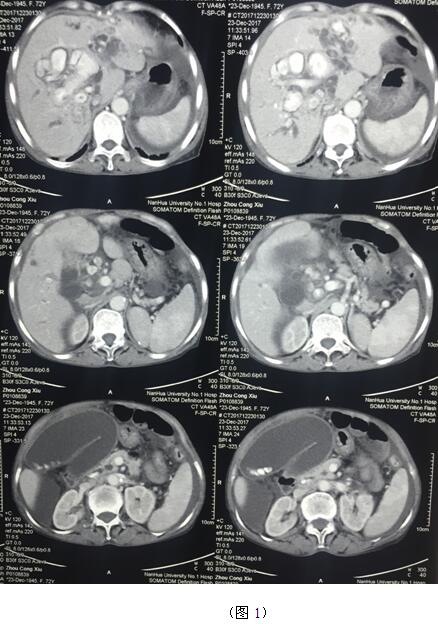

肝膽管結石疾病往往“鐘愛”貧困落后地區(qū)的病人,70多歲的周奶奶患全肝結石多年,由于家庭困難一直沒有得到有效治療,這個月病情惡化出現(xiàn)化膿性膽管炎并肝功能衰竭(圖1)。轉(zhuǎn)輾衡陽市內(nèi)多家醫(yī)院,不是因高昂的治療費用止步于院外,就是被以“病入膏肓”為由推脫出院。家屬經(jīng)過多方打聽得知衡陽市中心醫(yī)院是市里面的仁濟醫(yī)院,肝膽外科還是省級重點??疲覍偌安∪藨阎詈蟮南M麃淼搅酸t(yī)院肝膽外科。